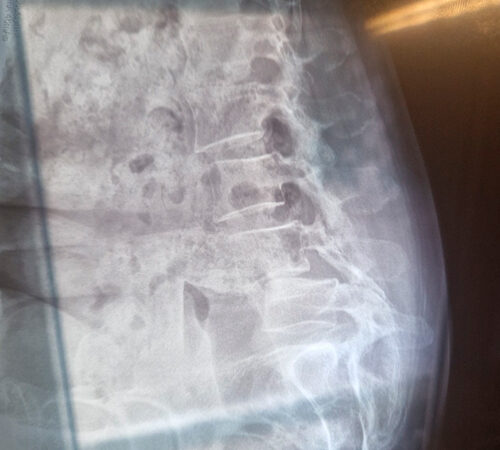

DIAGNOSI:

SPONDILOLISTESI LOMBARE CON STENOSI FORAMINALE

Risonanza magnetica lombare pre-operatoria

Intervento chirurgico eseguito:

PROCEDURA TLIF: TRANSFORAMINAL LUMBAR INTERBODY FUSION

Stabilizzazione percutanea di L4-L5 + introduzione di cage intersomatica TLIF Radiografia post-operatoria